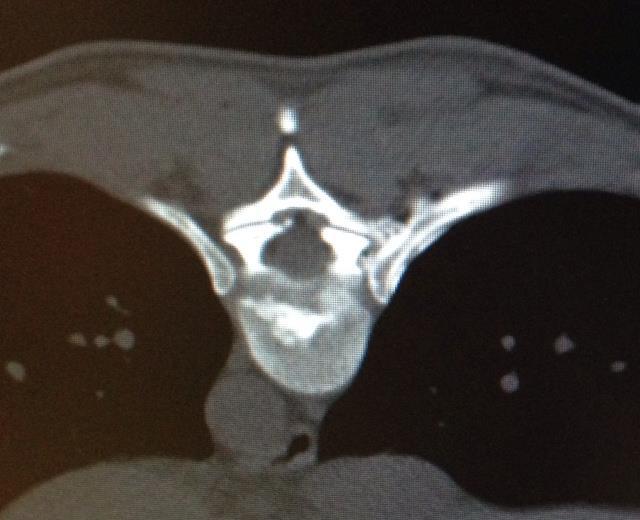

Bei einer Verödung der Bandscheibe werden in einer Sitzung auch die schmerzhaften Wirbelgelenke mitbehandelt.